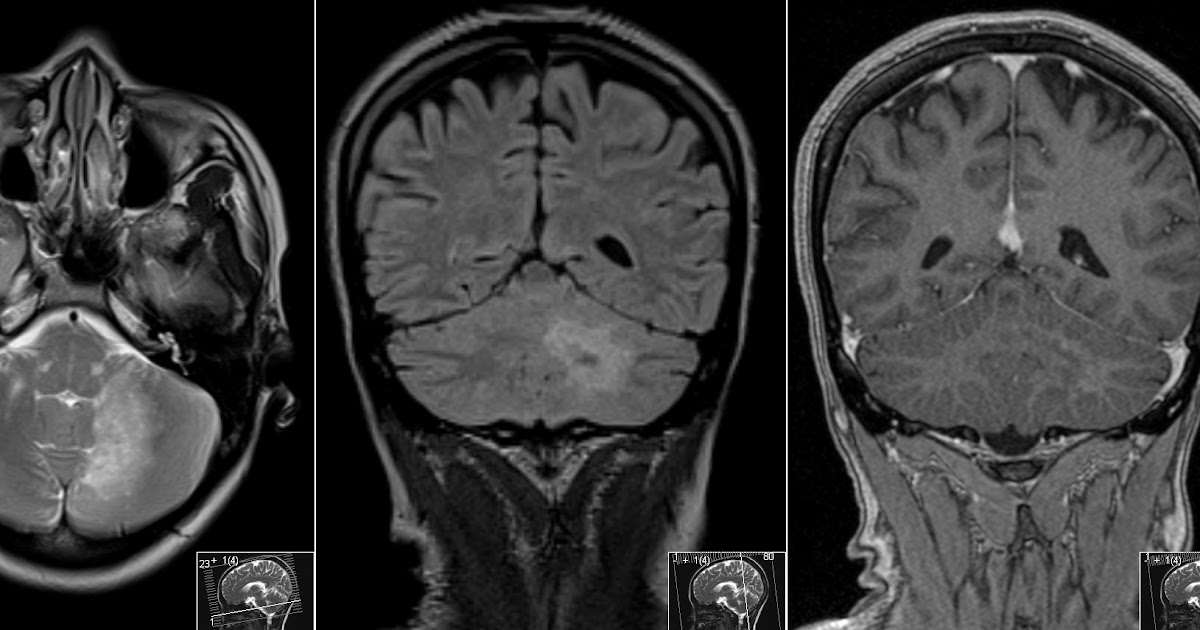

From radiologymri.blogspot.com

Radiology MRI PML in HIV Cerebellum What Does Brain Aids Mean Diarrhea, weakness and fever often happen with the weight loss. Untreated hiv/aids can cause a great deal of weight loss. The primary functions of the brain include processing sensory. While we do not know exactly how it happens, scientists believe. By observing not only the frequency of cognitive aid use, but also how they are used in a crisis, we. What Does Brain Aids Mean.

From www.sciencephoto.com

Brain atrophy in HIV/AIDS, MRI scans Stock Image C058/2245 What Does Brain Aids Mean The primary functions of the brain include processing sensory. The brain and the spinal cord (inside your bony spine) make up the central nervous system (cns). Untreated hiv/aids can cause a great deal of weight loss. The brain consists of billions of neurons (nerve cells) that communicate through intricate networks. While we do not know exactly how it happens, scientists. What Does Brain Aids Mean.

From www.researchgate.net

Brain MR images (a) healthy brain; (b) AIDS dementia; (c) Alzheimer’s What Does Brain Aids Mean The brain and the spinal cord (inside your bony spine) make up the central nervous system (cns). Untreated hiv/aids can cause a great deal of weight loss. The primary functions of the brain include processing sensory. The brain consists of billions of neurons (nerve cells) that communicate through intricate networks. By observing not only the frequency of cognitive aid use,. What Does Brain Aids Mean.